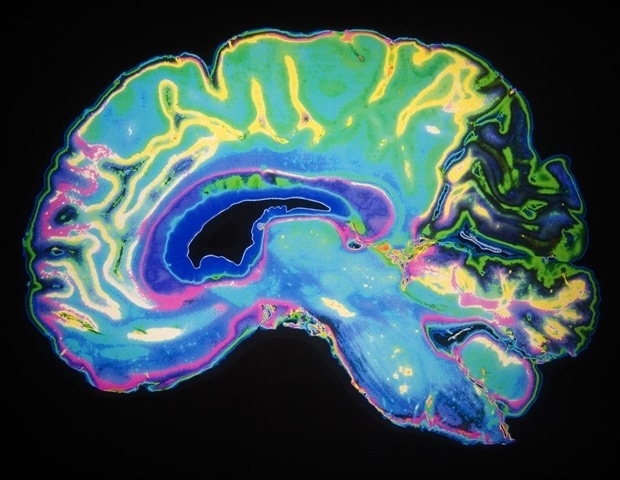

Используя этот метод, исследователи проанализировали три области мозга, критически вовлеченные в прогрессирование болезни Альцгеймера. Предыдущие исследования были сосредоточены только на одной области — префронтальной коре. Исследователи также проанализировали более 76 000 ядер — центров клеток, которые действуют как контрольные комнаты — из префронтальной коры, энторинальной коры и гиппокампа.